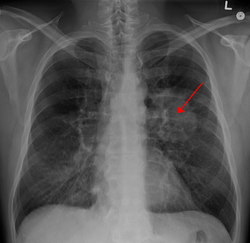

![]() Döş qəfəsinin rentgenindən ağciyərdəki şiş görünür (oxla göstərilib) | |